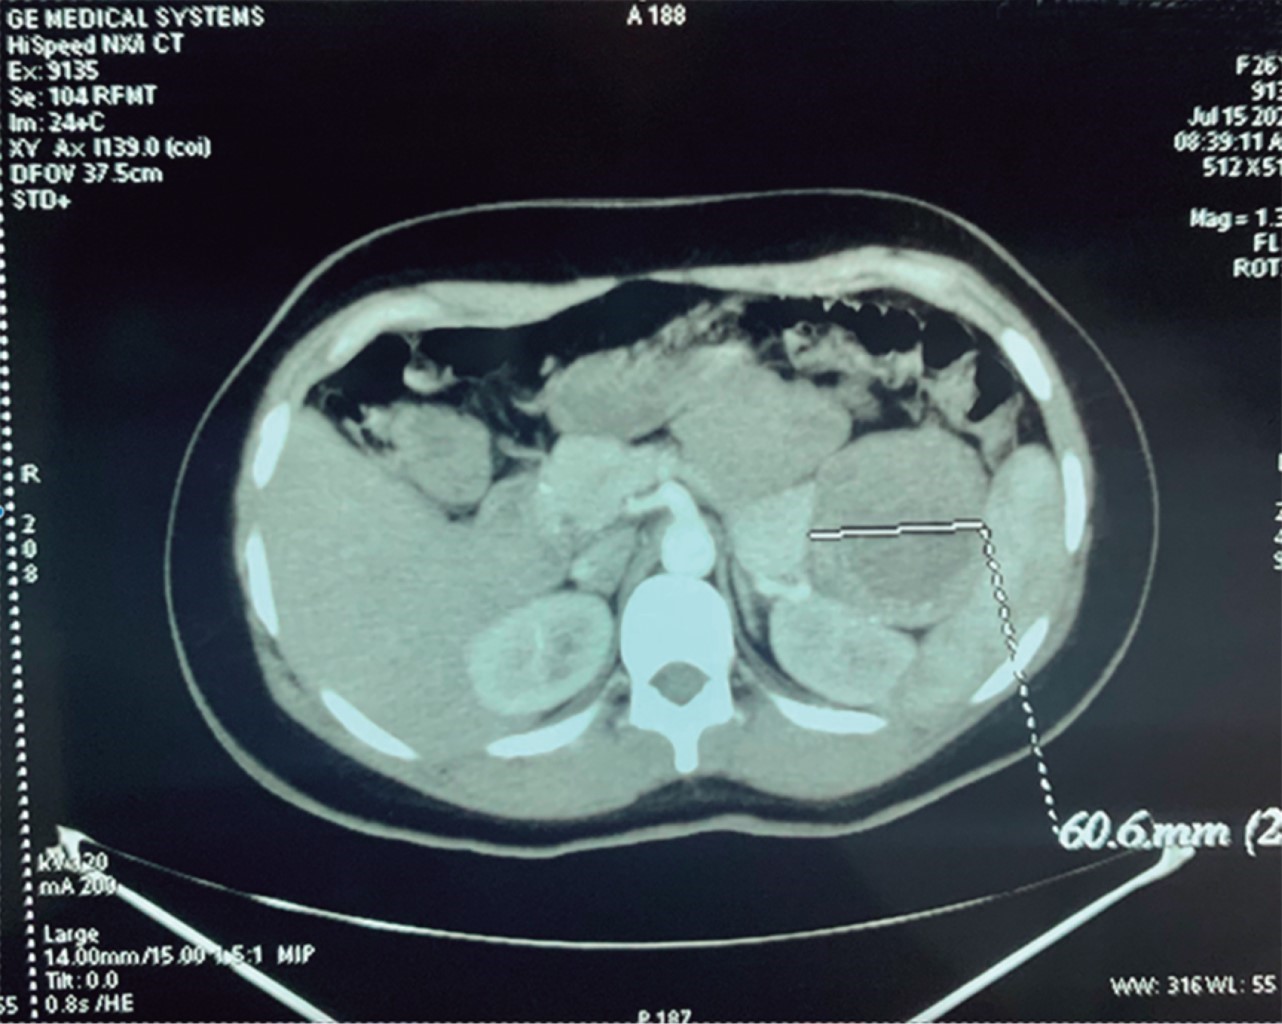

Se realizaron estudios paraclínicos laboratoriales y de imagen, se encontraron laboratorios sanguíneos (biometría hemática, química sanguínea, pruebas de función hepática, Tp, TpT, electrólitos séricos, amilasa, lipasa) sin alteraciones, al igual que la radiografía de tórax; sin embargo, se solicitó TC de abdomen superior, inferior y pélvico simple y con contraste bifásico no contrastado con enfoque diagnóstico, y como único hallazgo se reportó "bazo de tamaño normal; sin embargo, existe masa con 40 unidades Hounsfield con calcificaciones en la pared, bien delimitada, localizada en el hilio esplénico que mide aproximadamente 8.2 cm por 6.6 cm" (Figura 4). Se decide intervenir quirúrgicamente.

Figura 4